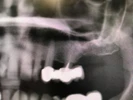

Periimplantitis

Gömülü Dişler

Lezyonlu (Enfekte) Diş